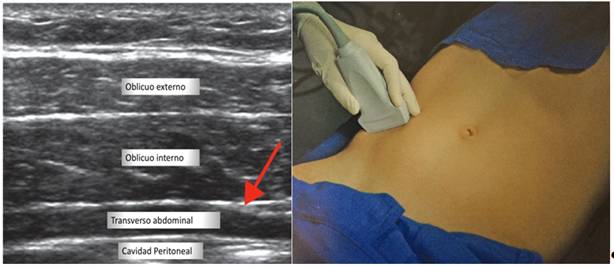

Bloqueo de nervios ilioinguinal e iliohipogástrico ecoguiado (figura 5), con sonda recta de alta frecuencia y aguja ecorrefringente de 100 mm (Pajunk®).

Figura 5 A izquierda, se muestra la imagen ecográfica del plano (flecha roja) para bloquear los nervios ilioinguinal e Ilioinguinal. A derecha, la posición de la sonda ecográfica para obtener la imagen.

Para bloquear estos nervios identificamos la espina ilíaca anterosuperior, ligamento inguinal y ombligo. Se realizó un examen sonográfico de la región inguinal y localizamos los nervios entre los músculos oblicuo interno y transverso. Administramos 5 ml de bupivacaína al 0.5% en cada nervio.